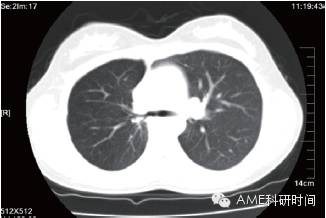

女,18岁,因为活动后因心悸伴气短半年余,间伴有干咳,而在2013年5月18日入院。入院后做胸部CT提示右中肺不张(图1),纤支镜检查示提示右主支气管开口肿物,病理活检结果提示“支气管粘液表皮样癌”(图2A)。做好手术前准备,2013年6月5日,在手术室全麻下行VATS右中下肺支气管袖状肺叶切除,淋巴结摘除术,术中见右中下肺阻塞性肺不张,右上肺过度胀气膨胀,气管旁隆突下淋巴结有肿大,予行右中下肺支气管袖状肺叶切除,淋巴结摘除(视频1)。气管断端送冰冻病理检查,结果示“未见癌残留”。术后病理结果示“支气管粘液表皮样癌”(图2B),第2,4,7,8,11,12组淋巴结未见转移癌。手术后给予抗炎及对症治疗,恢复良好,术后第10天出院。手术后1个月,复查胸部CT扫描,显示右上叶支气管通畅(图3)。

(图3 术后复查胸部CT扫描显示右上肺支气管通畅。)